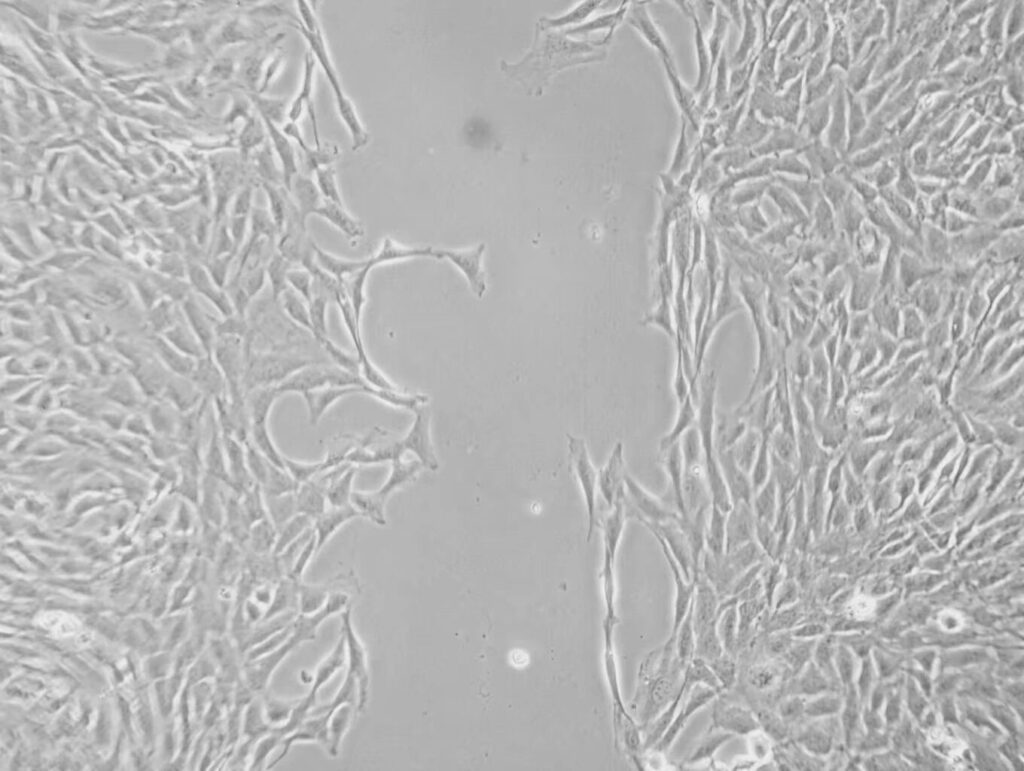

The study employed Boyden chamber assays and wound healing assays (scratch assays) to quantitatively assess the migration ability of VSMCs.

The success of the experiments relied heavily on Mshot MF53-N inverted fluorescence microscope, which helped the team capture images of wound healing at 0 hours and 24 hours, allowing them to calculate the migration distance of the cells.

With its high-definition imaging and long working distance, MF53-N enabled the researchers to clearly observe the migration of vascular smooth muscle cells at different time points, providing powerful data support for hypertension vascular remodeling research.